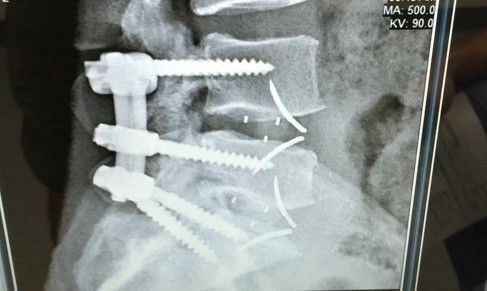

HOLY CRAP DUDE.......YOU GOT SCREWED!Here's my new titanium hardware. Should I compare it to the material that it replaced?

View attachment 135538View attachment 135539View attachment 135540